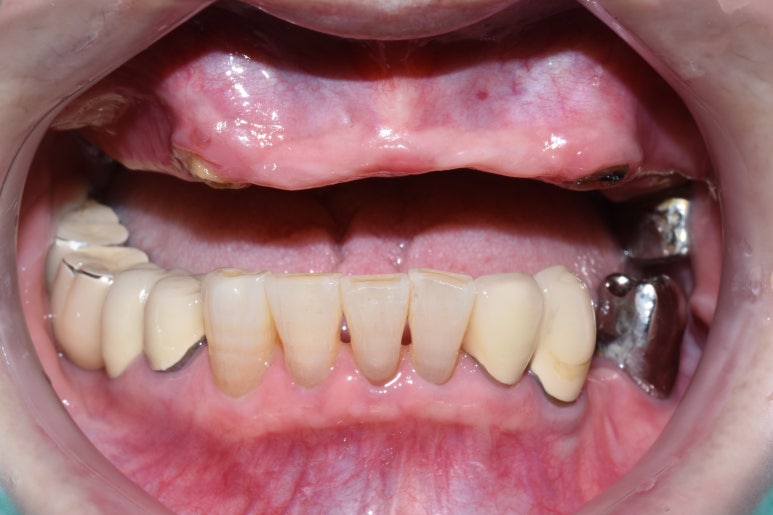

- 기초 수급자 환자 흔들리는 위 치아 빼고 위 전체 틀니,

아래쪽 어금니는 씹을 수 있게 최소 개수의 임플란트

- 오래된 상악틀니 → 2. 틀니제거시 모습 → 3.상악전체 임플란트

- 오래된 틀니를 새 전체틀니로, 아래앞니 부위는 임플란트

오래된 상악틀니를 상악 전체 틀니로 교체

아래 앞니부위 임플란트까지 한 후